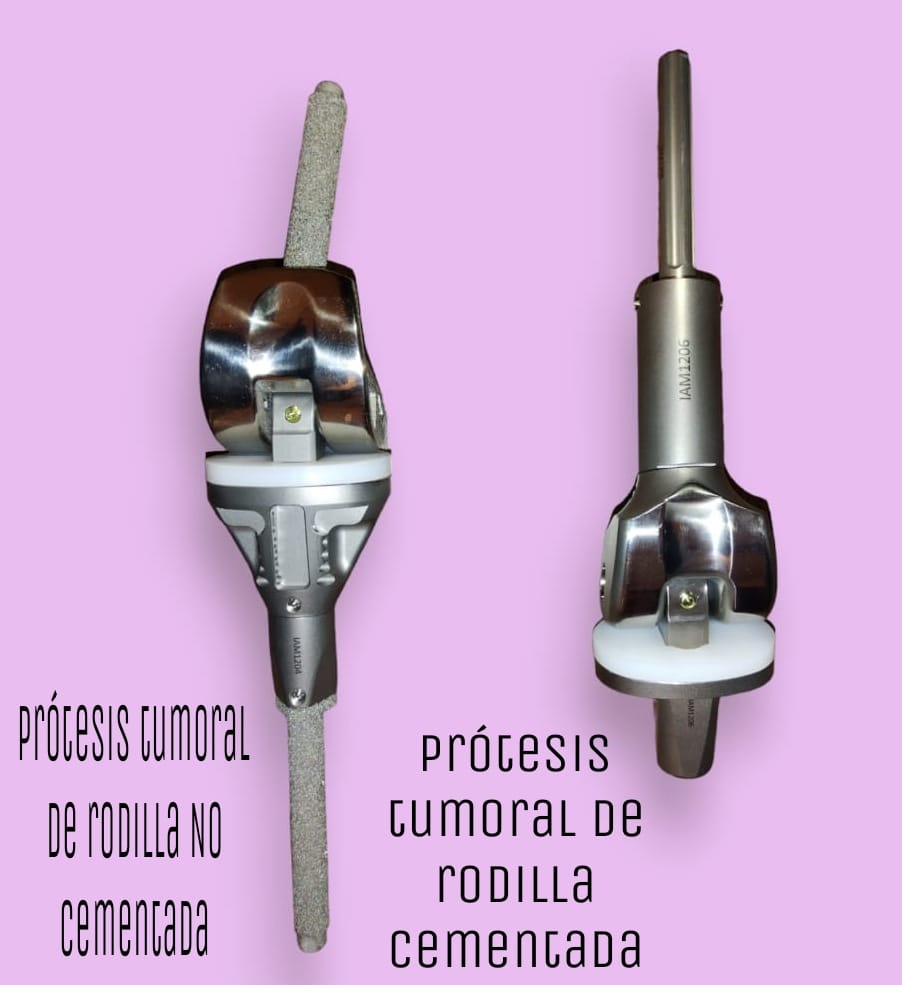

Permite el diseño y fabricación de implantes de cadera, rodilla, prótesis no convencionales para rescate de miembros, acetábulos y espaciadores.

Traumatología y Ortopedia

Diseño y fabricación de implantes ortopédicos personalizados para cadera, rodilla y rescate de miembros, optimizando la recuperación del paciente.